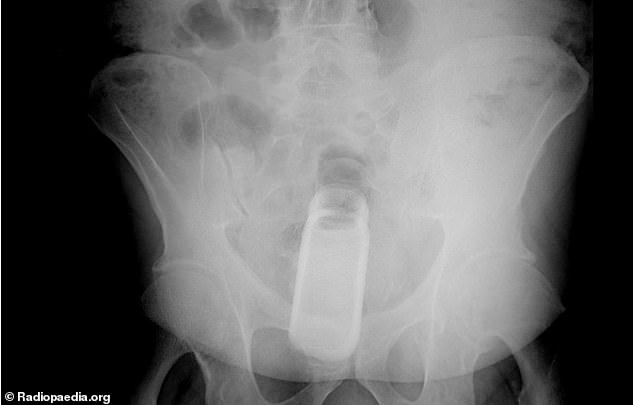

8. Ένα μπουκαλάκι αρώματος deoderant